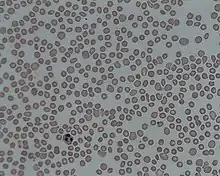

| A photomicrograph of the blood showing thrombocytopenia | |